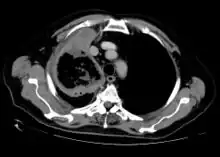

Imaging is often performed, such as CT scan of lungs and sinuses.[38] Signs on chest CT scans, such as nodules, cavities, halo signs, pleural effusion and wedge-shaped shadows, showing invasion of blood vessels may suggest a fungal infection, but does not confirm mucormycosis.[16] A reverse halo sign in a person with a blood cancer and low neutrophil count, is highly suggestive of mucormycosis.[16] CT scan images of mucormycosis can be useful to distinguish mucormycosis of the orbit and cellulitis of the orbit, but imaging may look identical to those of aspergillosis.[16] MRI may also be useful.[39]

CT head (axial): invasion of right maxillary sinus (presented with double vision, swollen painful eye).

CT head (coronal) of same person.

CT scan chest of person treated for acute myeloid leukaemia, presented with cough, fever and shortness of breath.